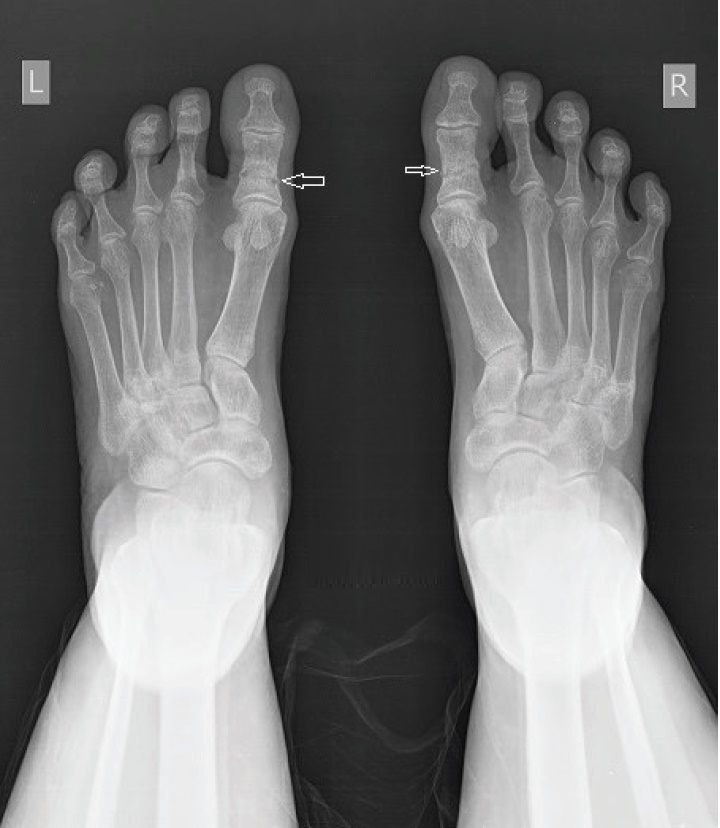

Radiological studies showed bilateral tibial shaft fractures, multiple fractures in bilateral tarsals (Figures 1 to 3). A PET Scan showed multiple insufficiency fractures of bilateral tibia, neck of right femur, metacarpal bones and scapula (Figures 4 to 7).

Click here to download Figure 1Figure 1.X-ray showing metatarsal fracture.

Figure 2.X-ray showing bilateral midshaft tibia fracture.

Figure 3.X-ray showing neck femure fracture on left side.